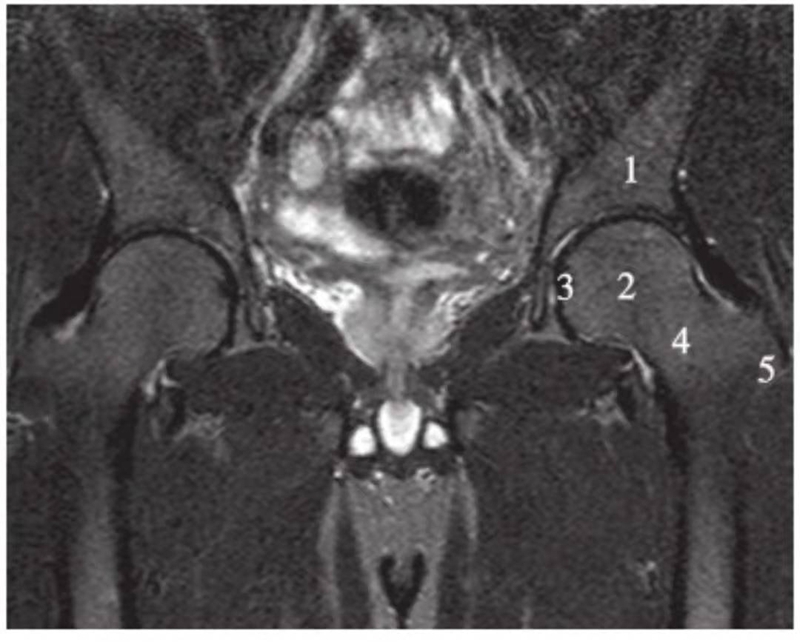

正常髋关节经股骨头中心层面T2WI像

1.股骨头;2.股骨颈;3.大转子;4.髂骨;5.臀小肌;6.臀中肌;7.闭孔内肌;8.闭孔外肌;9.股内侧肌;10.股外侧肌

正常髋关节经股骨头中心层面T2WI抑脂像

1.髂骨;2.股骨头;3.股骨头凹;4.股骨颈;5.大转子